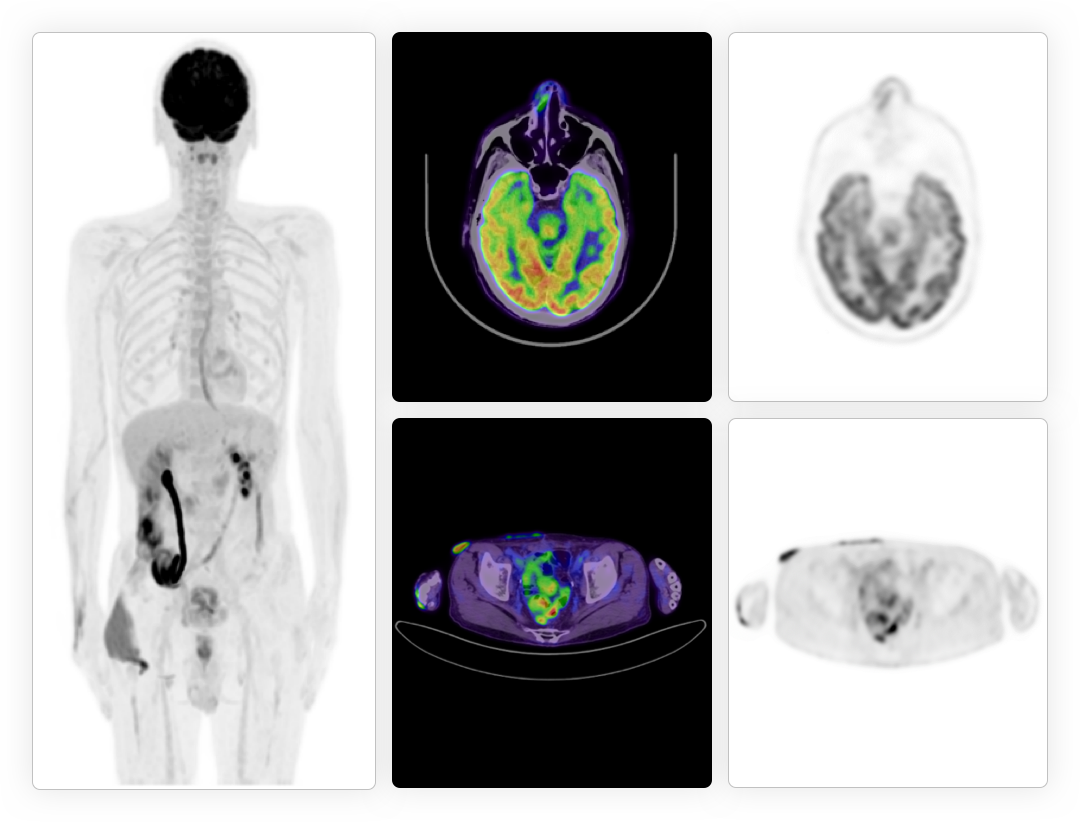

源头提升脑部精细解剖结构显像

大幅提升脑部图像信噪比,微小结构精确显像

基于原始数据自动识别运动轨迹,有效消除头部运动伪影

提供全脑智能神经高级分析*,辅助临床精准诊断

*uWS-MI后处理工作站提供高级脑分析应用